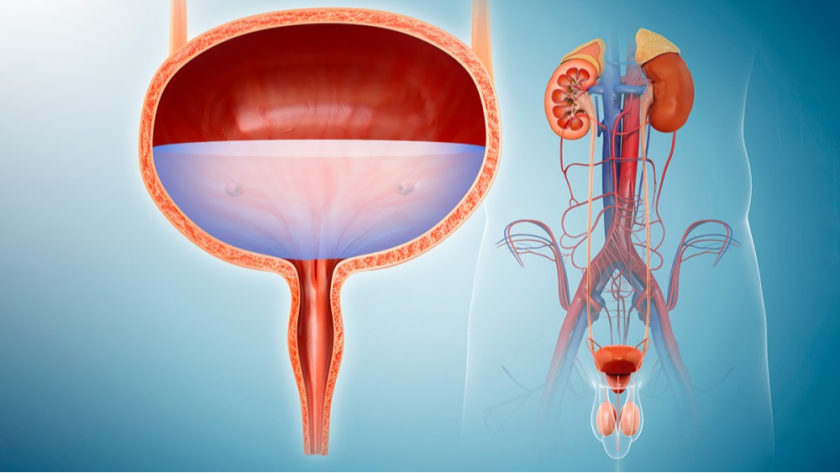

CSN Hospital (A unit of CSN Transparency Private Limited), was established in 2021 and in such a short span of time, it became one of the most respected hospitals in the State, and is also amongst the most preferred destinations for patients from several parts of the State. Our hospital specializes in cutting-edge medical procedures, spearheaded by experienced doctors who are skillfully supported by dedicated patient-care personnel.

Combining the best specialists and equipment to provide you nothing short of the best in healthcare